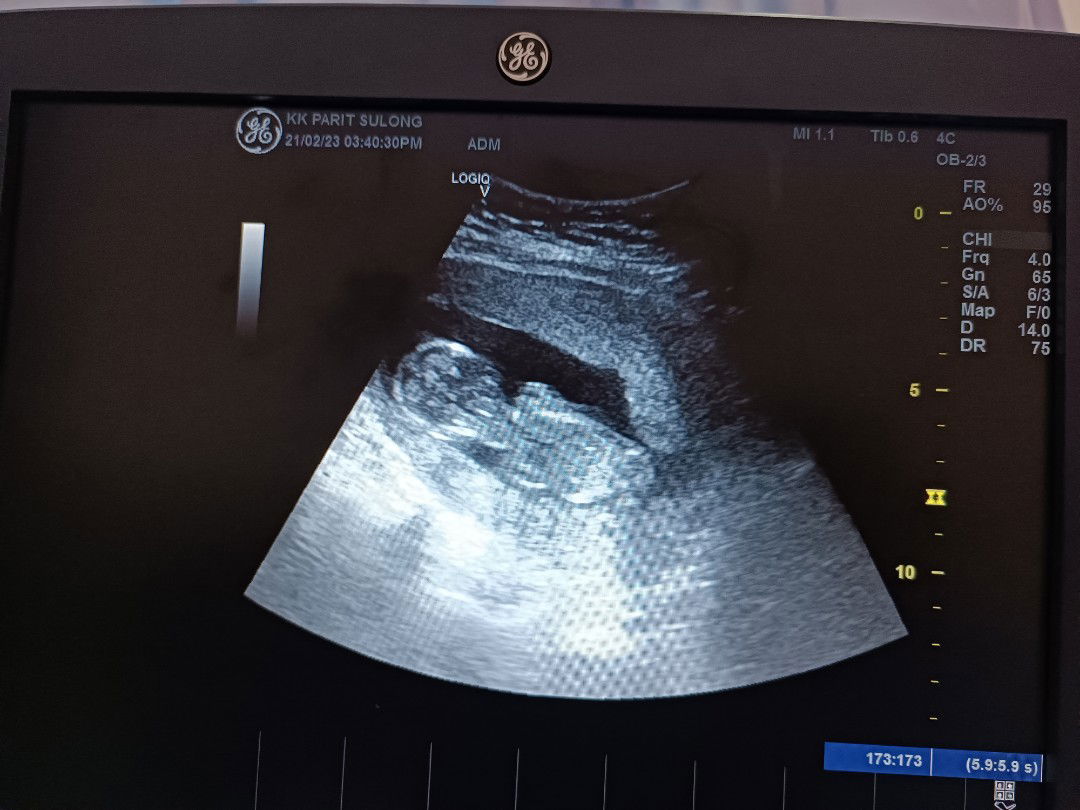

Saya praggy 6week.... Tadi scan... Ade nampak cyst saiz 4cm... Saya terus down...

Bahaya tak cyst semasa praggy??

Cyst ni akan mengecut seiring dgn tumbesaran baby.. Dgr ckp doktor n ubah gaya pemakanan hidup y sihat ok 😊

cyst bawah 5cm masih boleh mengecut sendiri dgn cara pemakanan dan gaya hidup yg sihat